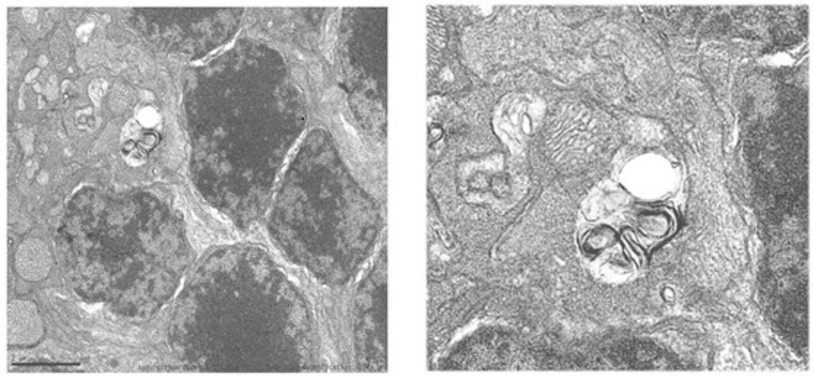

Deficiencia de ACOX2: Una alteración hereditaria en la síntesis de ácidos biliares identificada en un adolescente con hipertransaminasemia persistente